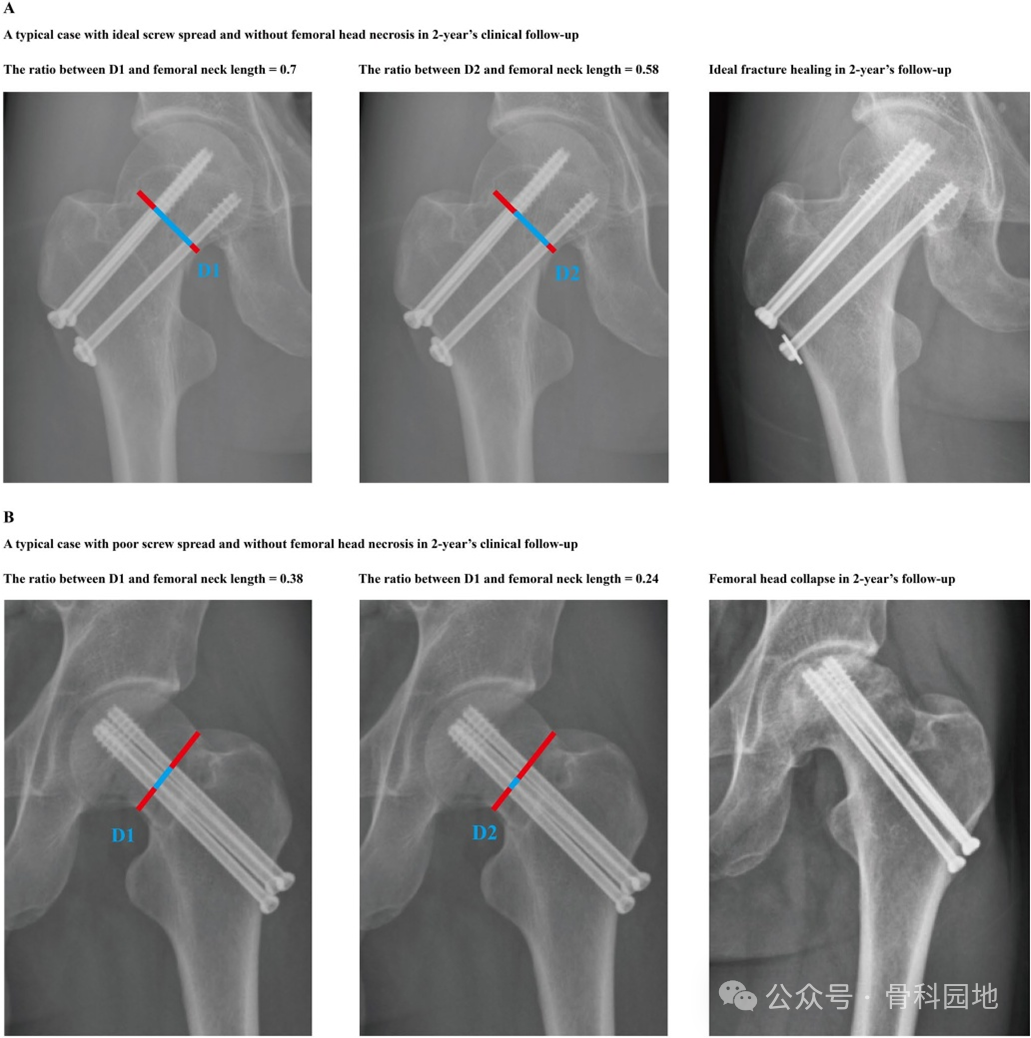

下图A螺钉分布理想,骨愈合,B螺钉分布不良,股骨头坏死。

本研究表明,通过优化固定稳定性,提高螺钉分散可以显著降低短期股骨头坏死的风险。